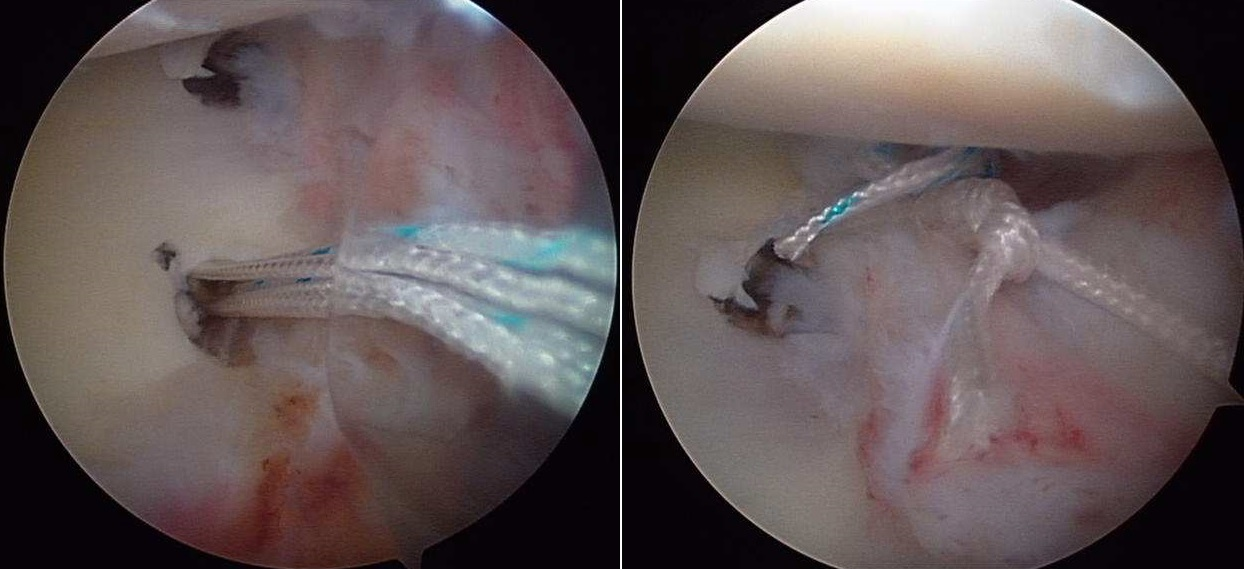

In the past 15 years improvements in arthroscopic techniques (small incisions to access the joint and small instruments controlled by microcameras) have greatly improved results. The advantage of not excising the muscles and the precision in repairing the tears makes this technique suitable for young patients (from 15 to 30 yrs of age), with a limited number of dislocations and with microinstablity. The technique uses “suture anchors” similar to microscrews (in titanium or resorbable polylactic acid) with nonresorbable highly resistant threads that are passed and tied to the joint capsule and to the glenoid labrum to recreate the normal capsular tension.